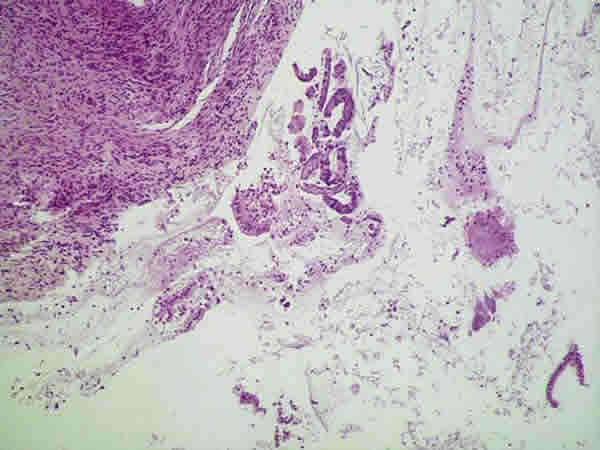

Fig 3: Material insuficiente compuesto por fragmento muscular, moco y tiras de epitelio cervical.